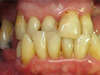

Consultation initiale pour prise en charge globale

Mise en place d’implants et de couronnes pour

les dents du bas